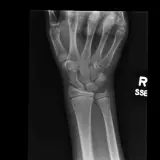

MSK Radiographs

Peds Radiographs